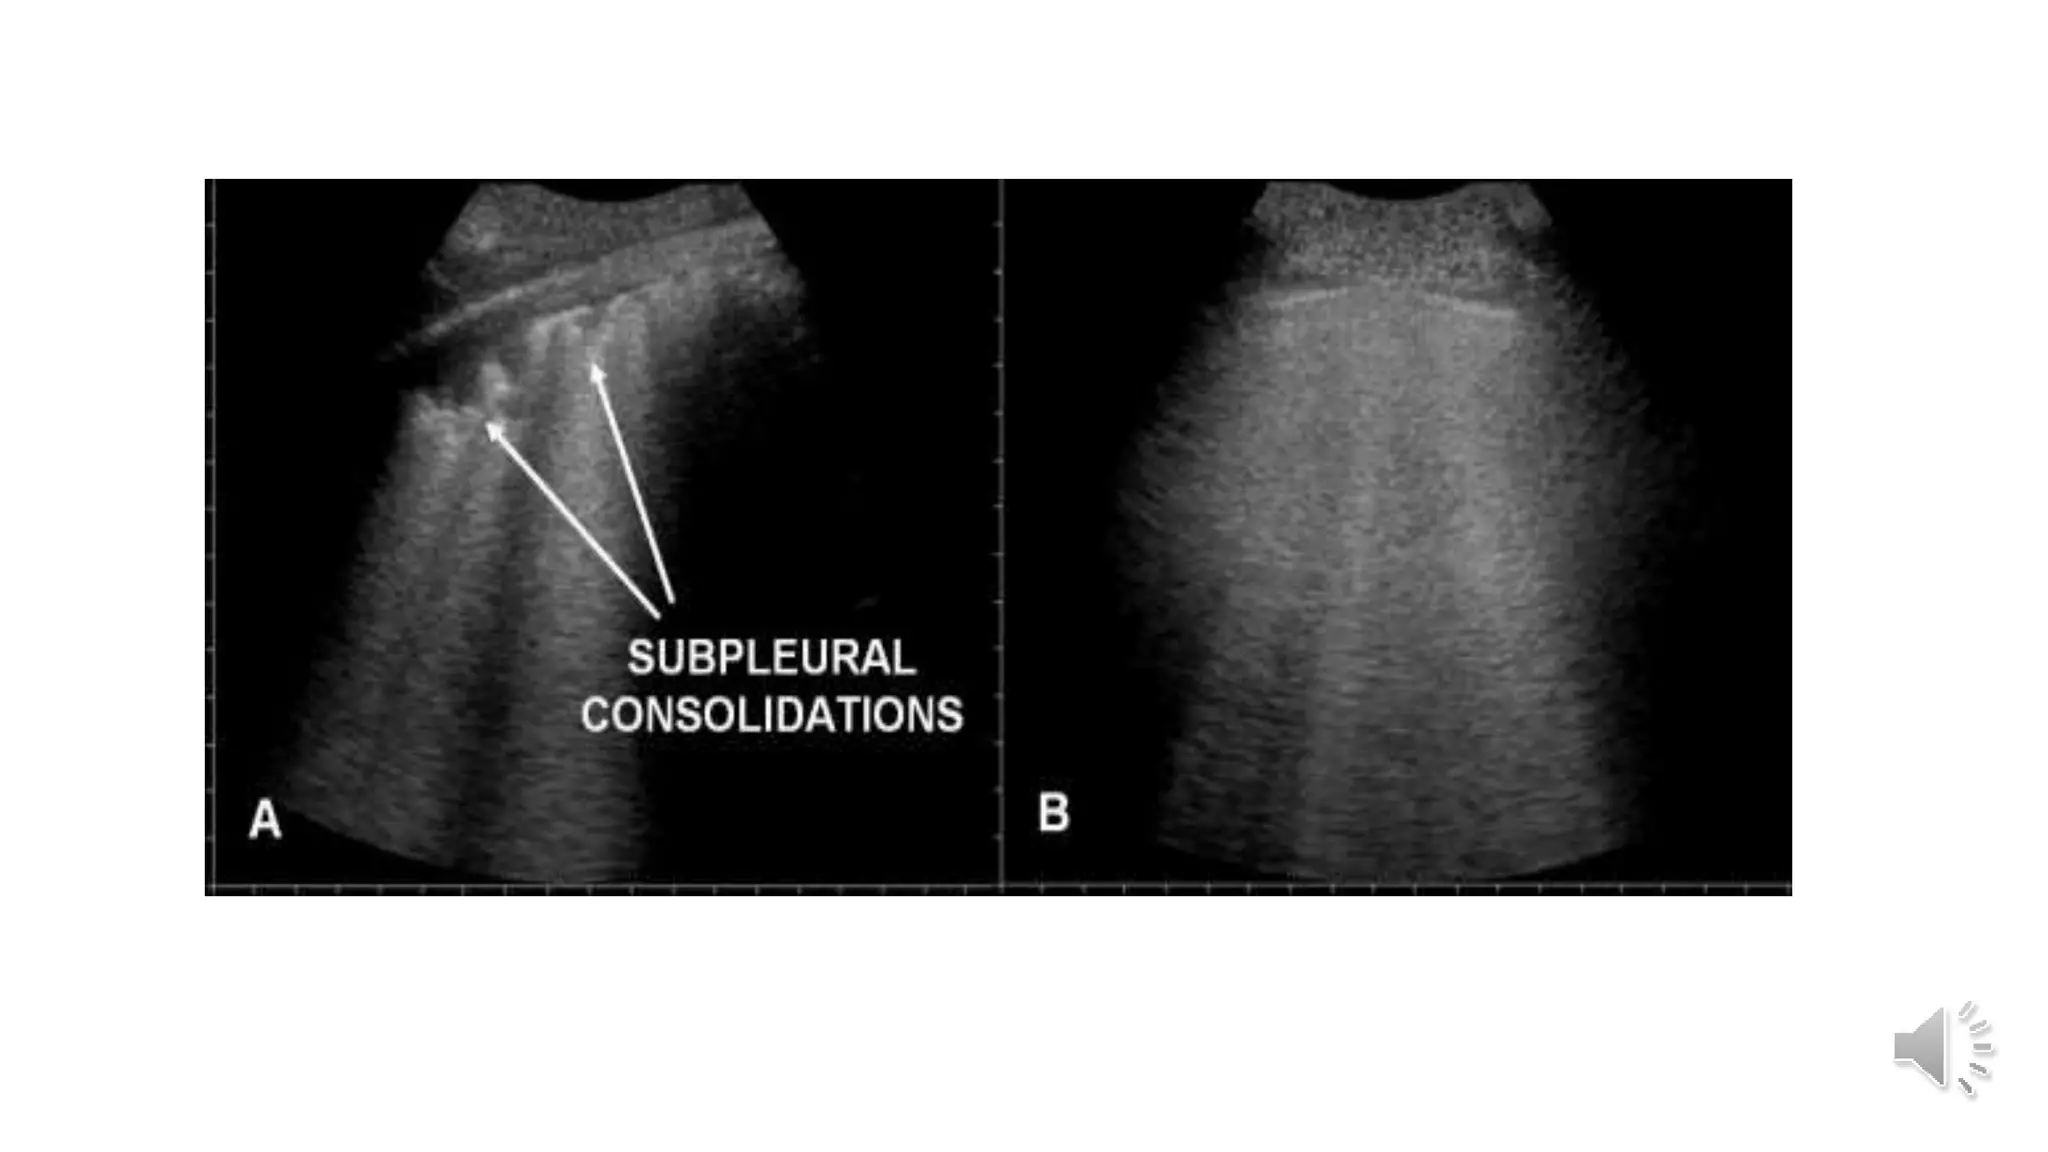

Table 5 CT and ultrasonographic features of COVID-19 pneumonia

Thickened pleura Thickened pleural line

Ground glass shadow and effusion B lines (multifocal, discrete, or confluent)

Pulmonary infiltrating shadow Confluent B lines

Subpleural consolidation Small (centomeric) consolidations)

Translobar consolidation Both non-translobar and translobar consolidation

No Pleural effusion No Pleural effusion

More than two lobes affected Multilobar distribution of abnormalities

Focal B lines is the main feature in the early stage and in

mild infection; alveolar interstitial syndrome is the main

feature in the progressive stage and in critically ill

patients; A lines can be found in the convalescence;

pleural line thickening with uneven B lines can be seen in

patients with pulmonary fibrosis